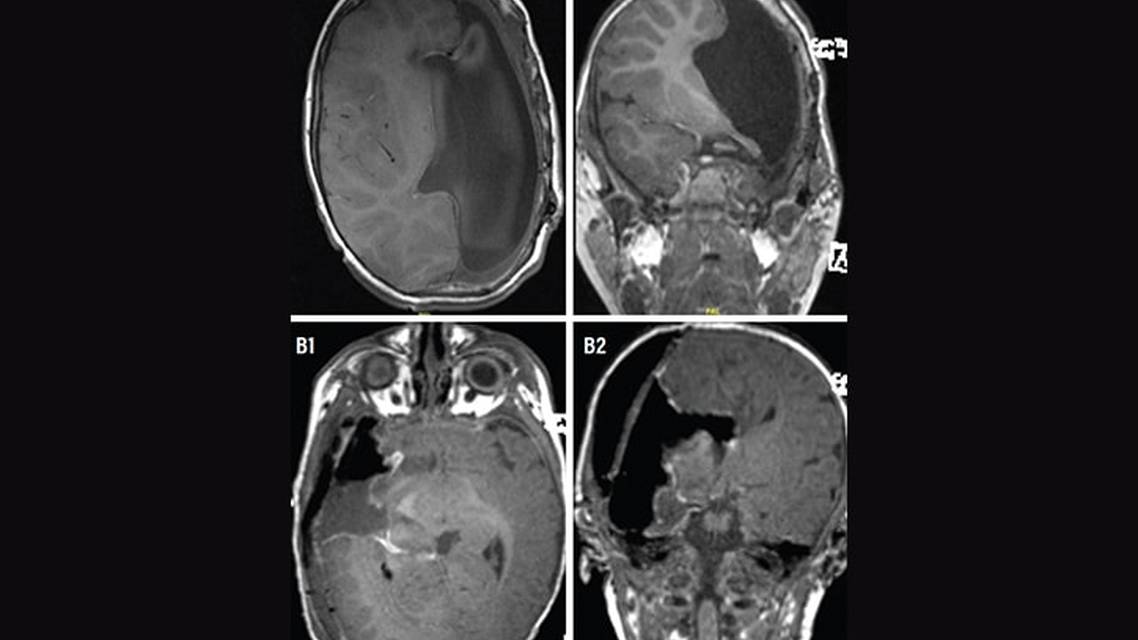

The first surgical technique developed was the anatomic hemispherectomy (AH), which involved removal of the entire cerebral hemisphere, at times also including the basal ganglia and thalamus. Modern surgeries typically attempt to achieve disconnection of the corona radiata, disconnection of the mesial temporal structures, total corpus callosotomy, and disconnection of the frontal horizontal fibers (Figure 1, Row A).7

Hemidecortication is the surgical removal of the cortex of one hemisphere while keeping the white matter intact and, therefore, the underlying ventricles unexposed; this was developed to avoid superficial hemosiderosis. Dr. Rasmussen further adapted this technique to what is called a functional hemispherectomy (FH); in this procedure, disconnection of the corpus callosum and upper brainstem is performed, as well as removal of the temporal lobe and central portion of frontoparietal lobe (Figure 1, Row B). This was adapted further in the 1990s to hemispherotomy, which is similar to a hemispherectomy but with less brain removed in order to reduce risk of complication, while still achieving disconnection of the affected hemisphere. Revision hemispherectomies may be chosen if the initial hemispherectomy does not lead to seizure freedom, presumably because of incomplete disconnection (although the possibility of contralateral hemispheric seizures must be ruled out). This may involve converting an FH to an AH, or performing further resection or disconnection of tissue that is suspected to remain connected.4,7